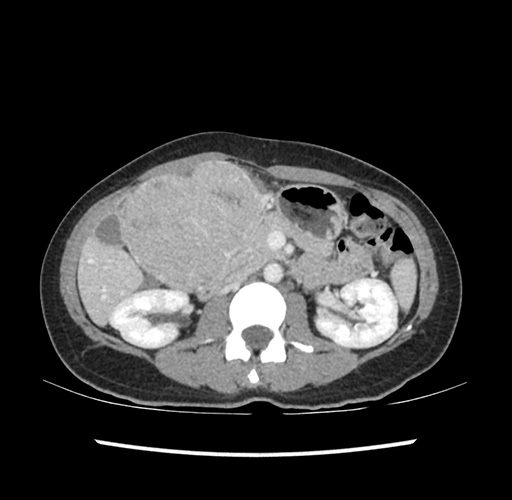

Imaging Analysis

Look through the patient's CT scan to identify any areas of concern for the necessary procedure.

Based on your CT findings, which issue(s) would give reason for "planned slowing down moment(s)" in this case?